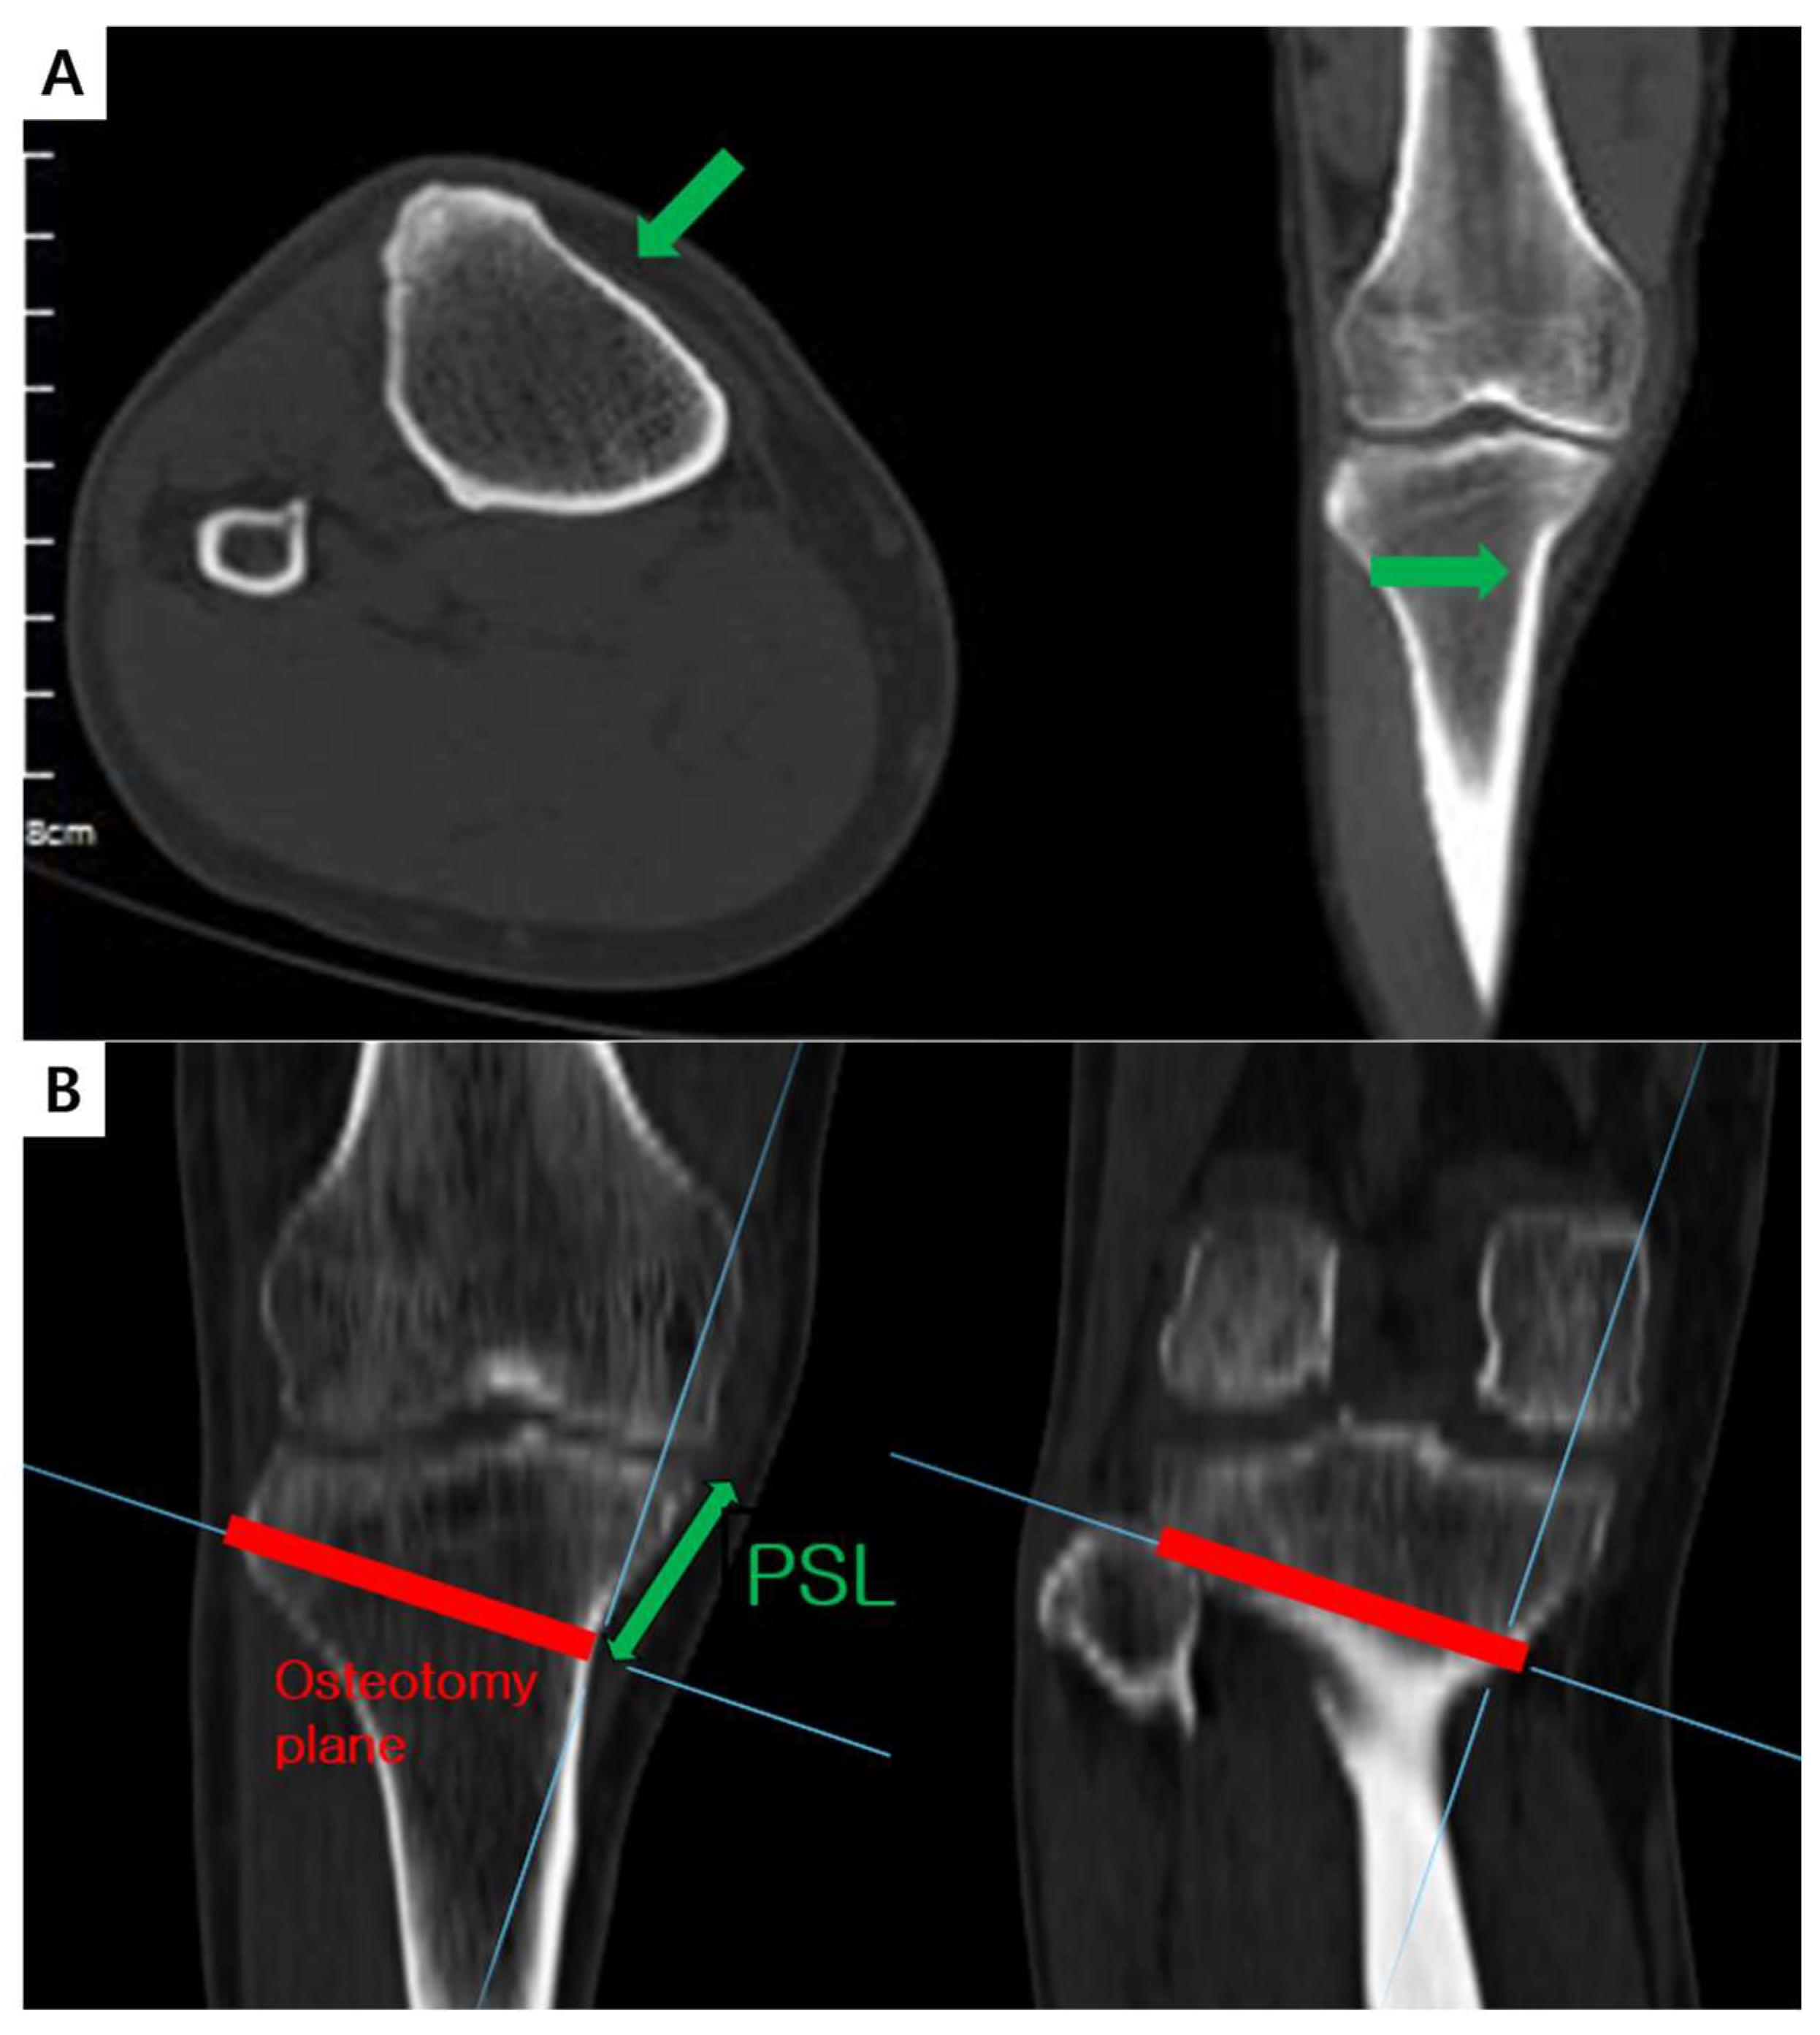

2.1. D-Hole Violation Simulation Study

3.1. D-Hole Violation Simulation